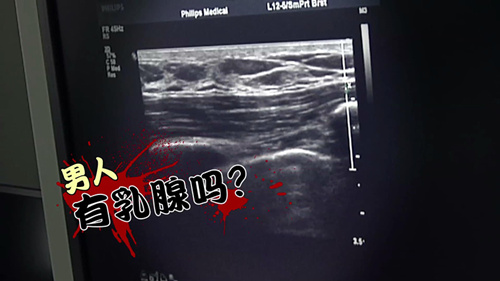

央视《是真的吗》截图

那男人到底有没有乳腺呢?中国解放军总医院超声诊断科副主任医师宋阳光介绍,乳腺是乳房内部的主要成分,男性的乳腺是不会像女性那样发育的,厚度大约是4个毫米,因此,成年男性乳腺的面积、厚度都要远远的小于成年女性。这也难怪很多人都误以为男人是没有乳腺。可是,男性的乳腺少,是不是就不会得乳腺癌了呢?中国人民解放军总医院普通外科乳腺专病中心主任医师王建东说:“那肯定是有乳腺才会得乳腺癌,男人是有乳腺的,所以男人是会得乳腺癌的,但是得癌的概率远远低于女性。”王建东还告诉记者,男性,由于雌激素很少,乳腺也几乎不发育。所以,患乳腺癌的几率要远低于女性。但也并不排除男性患病的可能性。有资料显示,男性在乳腺癌患者中的占比约为百分之一。可是,虽然男人患乳腺癌的几率并不高,但一旦患了这种疾病,同样需要进行化疗、切除等治疗。